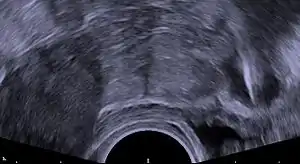

Procedure

During the insertion procedure, health care providers use a speculum to find the cervix (the opening to the uterus), pinch the cervix to stabilize it open with a tenaculum,[72] and then use an insertion device to place the IUD in the uterus. The insertion device goes through the cervix. The procedure itself, if uncomplicated, should take no more than five to ten minutes.[73]

For immediate postpartum insertion, the IUD is inserted following the removal of the placenta from the uterus. The uterus is larger than baseline following birth, which has important implications for insertion. After vaginal deliveries, insertions can be done using placental forceps, a longer inserter specialized for postpartum insertions, or manually, where the provider uses their hand to insert the IUD in the uterus. After cesarean deliveries, the IUD is placed in the uterus with forceps or manually during surgery prior to suturing the uterine incision.[71][68][74]

Generally, the removal is uncomplicated and reported to be not as painful as the insertion because there is no instrument that needs to go through the cervix.[75] This process requires the health care provider to find the cervix with a speculum and then use ring forceps, which only go into the vagina, to grasp the IUD strings and then pull the IUD out.